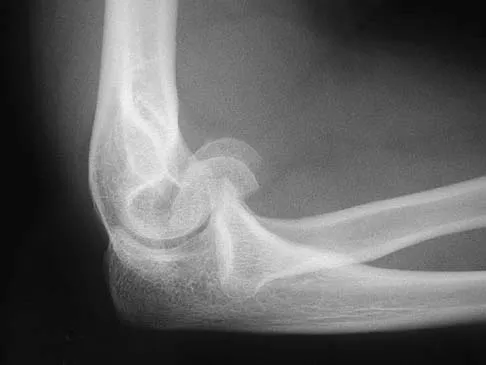

Question 12

Figure 12 shows a lateral radiograph of the elbow. What is the most likely diagnosis?

Explanation